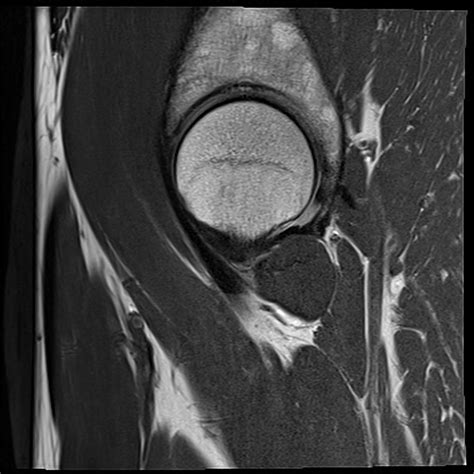

The MRI knee joint is widely considered the gold standard in diagnostic imaging for evaluating soft tissue injuries, chronic pain, and complex structural issues within the knee. Unlike traditional X-rays, which primarily display bone, magnetic resonance imaging provides a high-resolution, detailed view of ligaments, tendons, cartilage, and menisci. If you have been experiencing persistent knee discomfort, locking, or instability, your physician may recommend this non-invasive procedure to get a clearer picture of what is happening inside your joint.

By utilizing magnetic fields and radio waves, the machine generates cross-sectional images that allow radiologists to assess the structural integrity of the knee with extreme precision.

MRI Knee Joint Soft tissue & ligaments Unmatched detail for cartilage and tendons.